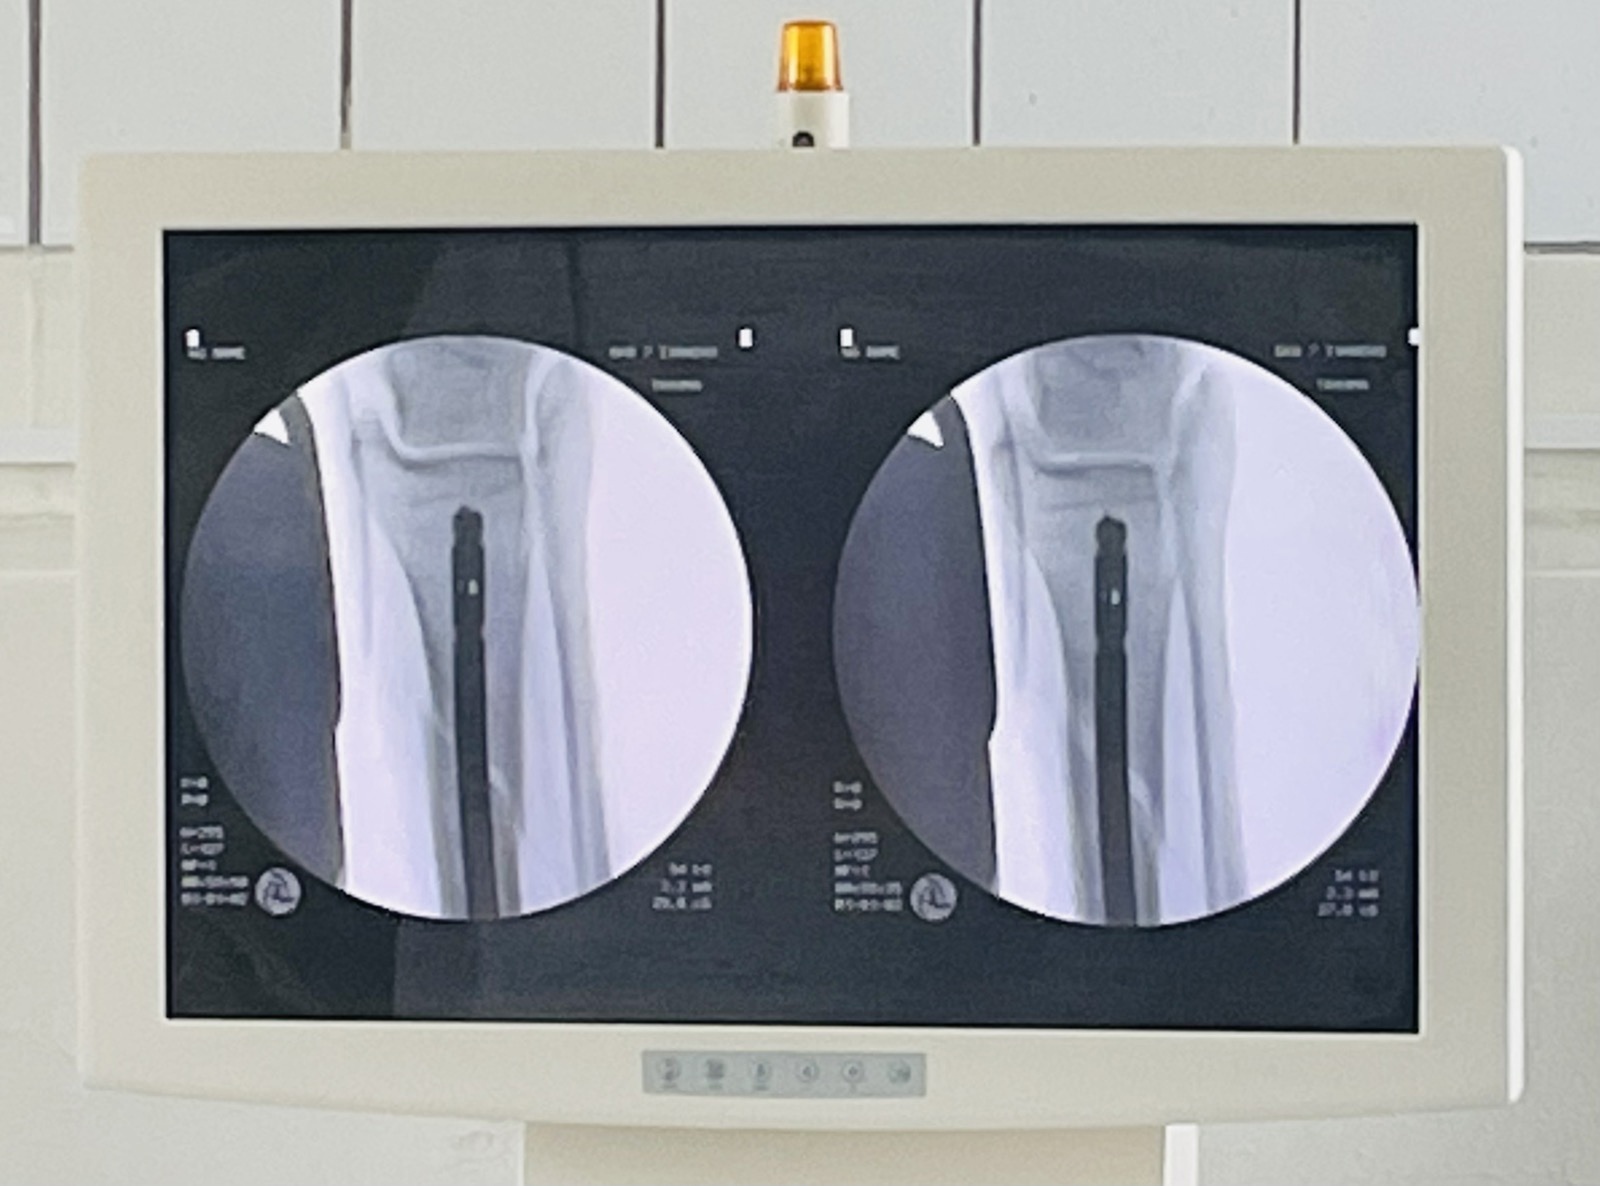

Врачи-травматологи седьмой горбольницы, сделав рентгеновский снимок, выявили перелом голени. Из-за того, что пациент не обратился в больницу сразу после неудачного падения, произошло смещение отломков и скопилась большая гематома. Врачи приняли решение о проведении операции. Специалисты отметили, что если бы друзья задержались на отдыхе еще на пару дней, то ногу пациенту нужно было бы ампутировать.